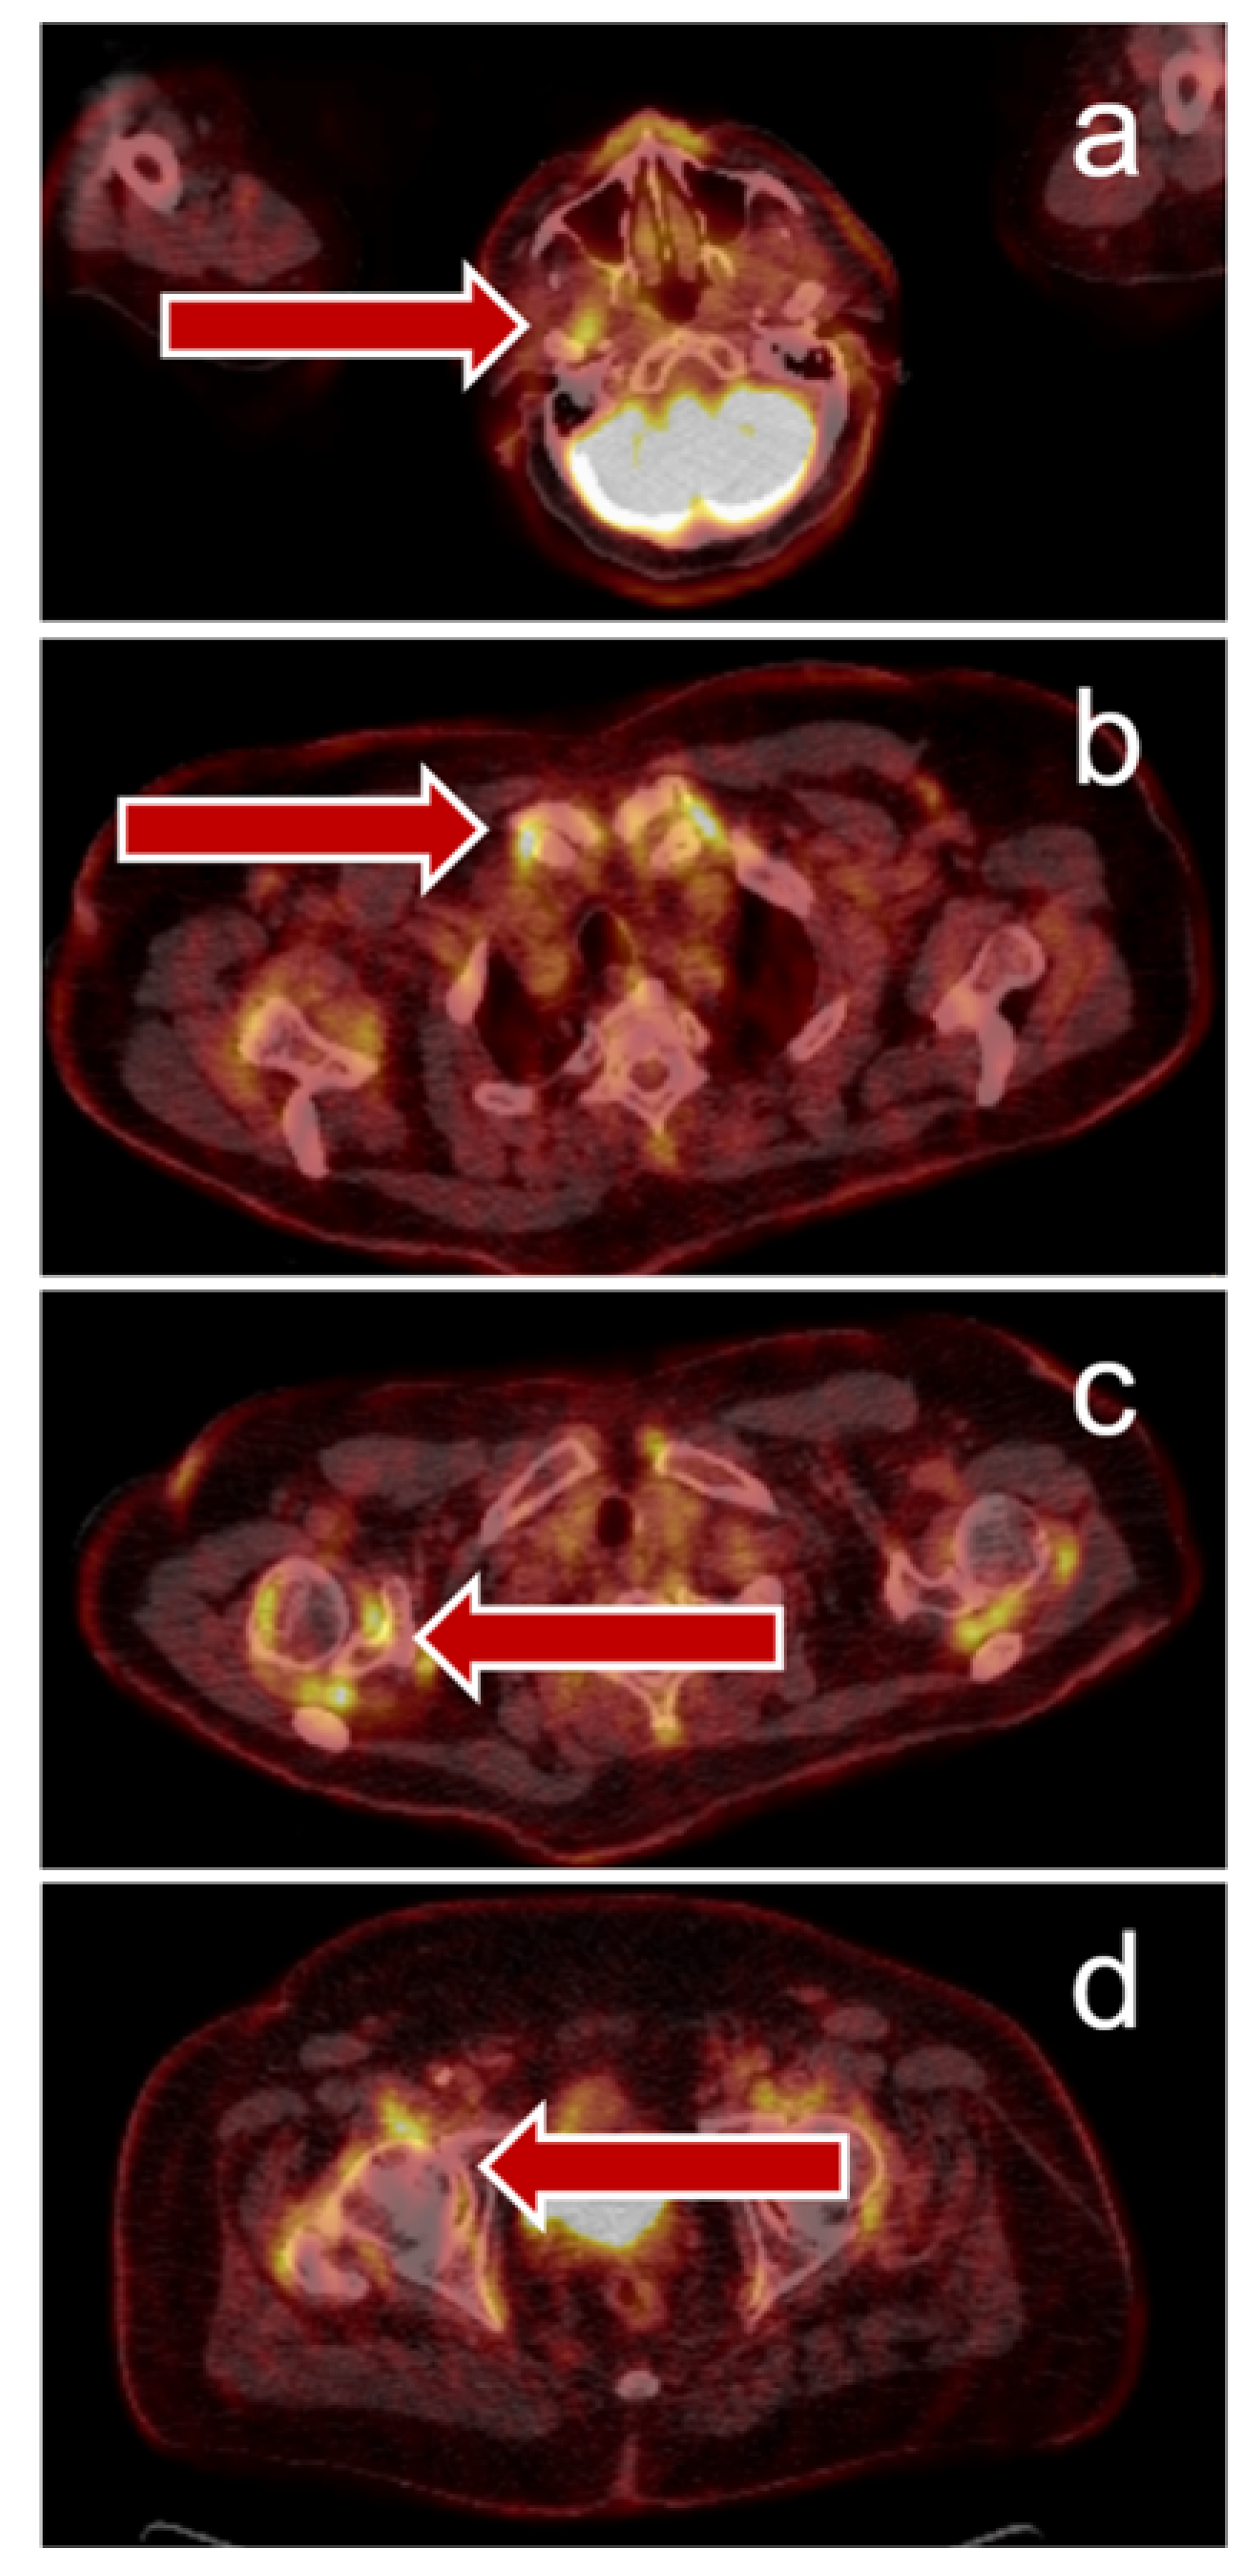

Figure 3.

Immune-related arthritis visualized by PET/CT: 69-year-old man with stage IV NSCLC (PD-L1 100%), small left hilar tumor, adrenal metastasis, and symptomatic brain metastasis – resected). The patient reported a history of chronic polyarthritis but did not require therapy at time of cancer diagnosis. The patient received six cycles of pembrolizumab monotherapy and reached partial remission. Due to increasing joint pain and suspected bone metastases, PET/CT was performed and showed a complete metabolic tumor remission, but hypermetabolic joint lesions ((a)–temporomandibular joints, (b)—sternoclavicular joints, (c)—shoulders, (d)—hips) compatible with immune-mediated arthritis. The patient received corticosteroid therapy and immunotherapy was paused, the joint pain improved.